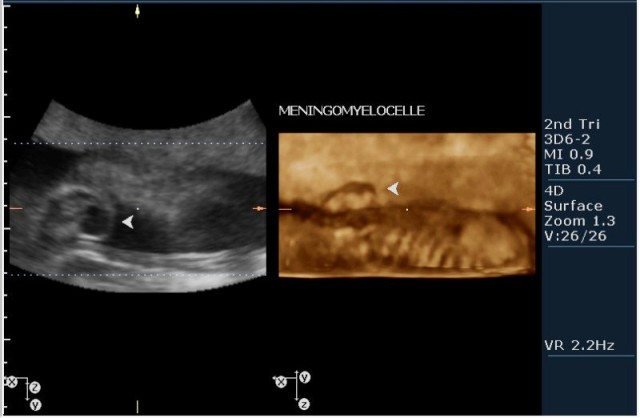

2.V-образное расщепление позвоночного столбы(рахисхизис)(на сонограмме №6 отчетливо виден дефект в поясничном отделе);

3.наличие дорсально расположенного содержимого спинномозгового канала(на сонограмме №7 видны мозговые оболочки).Это описывается как менингоцеле.

На сонограммах головы плода визуализаируется гифдроцефалия, патогенетически связанная со спинномозговой грыжей (менингомиелоцеле) представленная в 2D и 3D режимах. В режиме Skeleton не удалось получить "картинку презентационного качества", плод начал сильно вертется; но рекоммендация очень грамотная :idea: , спасибо за ваш пост!